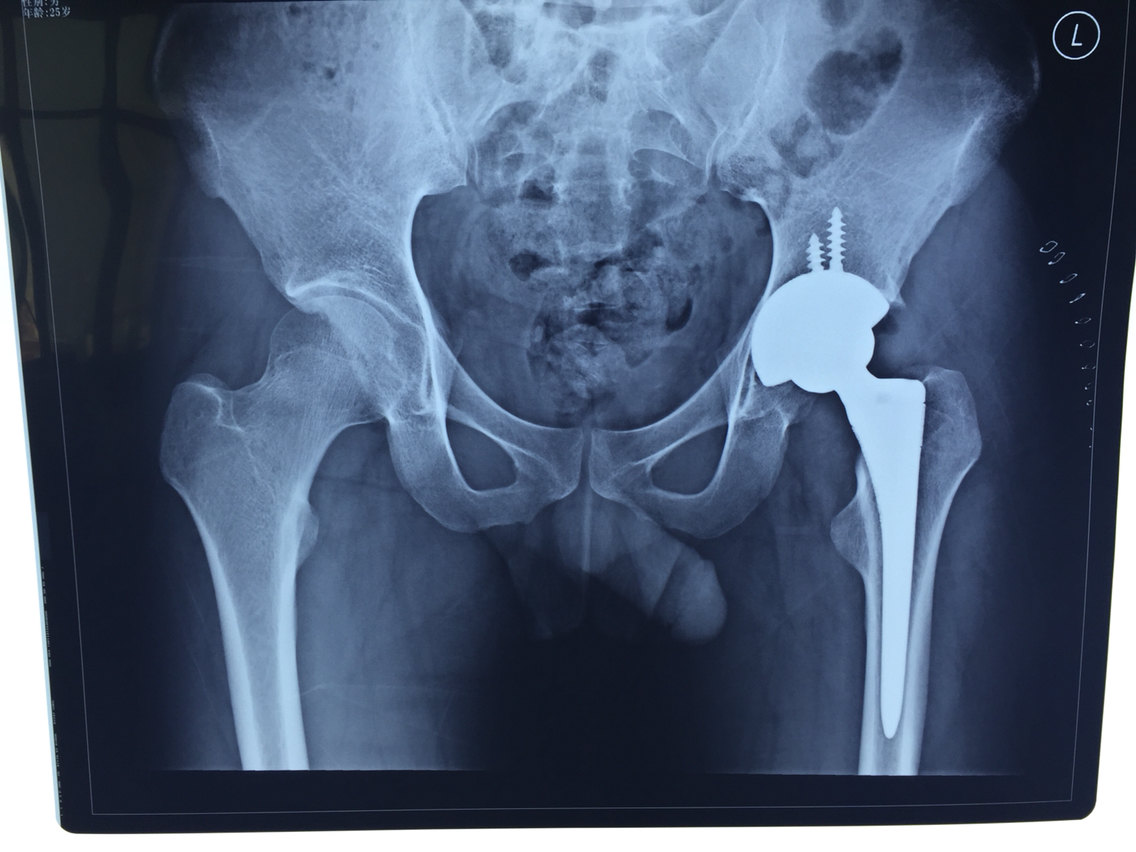

股骨颈骨折该选择怎样的治疗 内固定还是关节置换